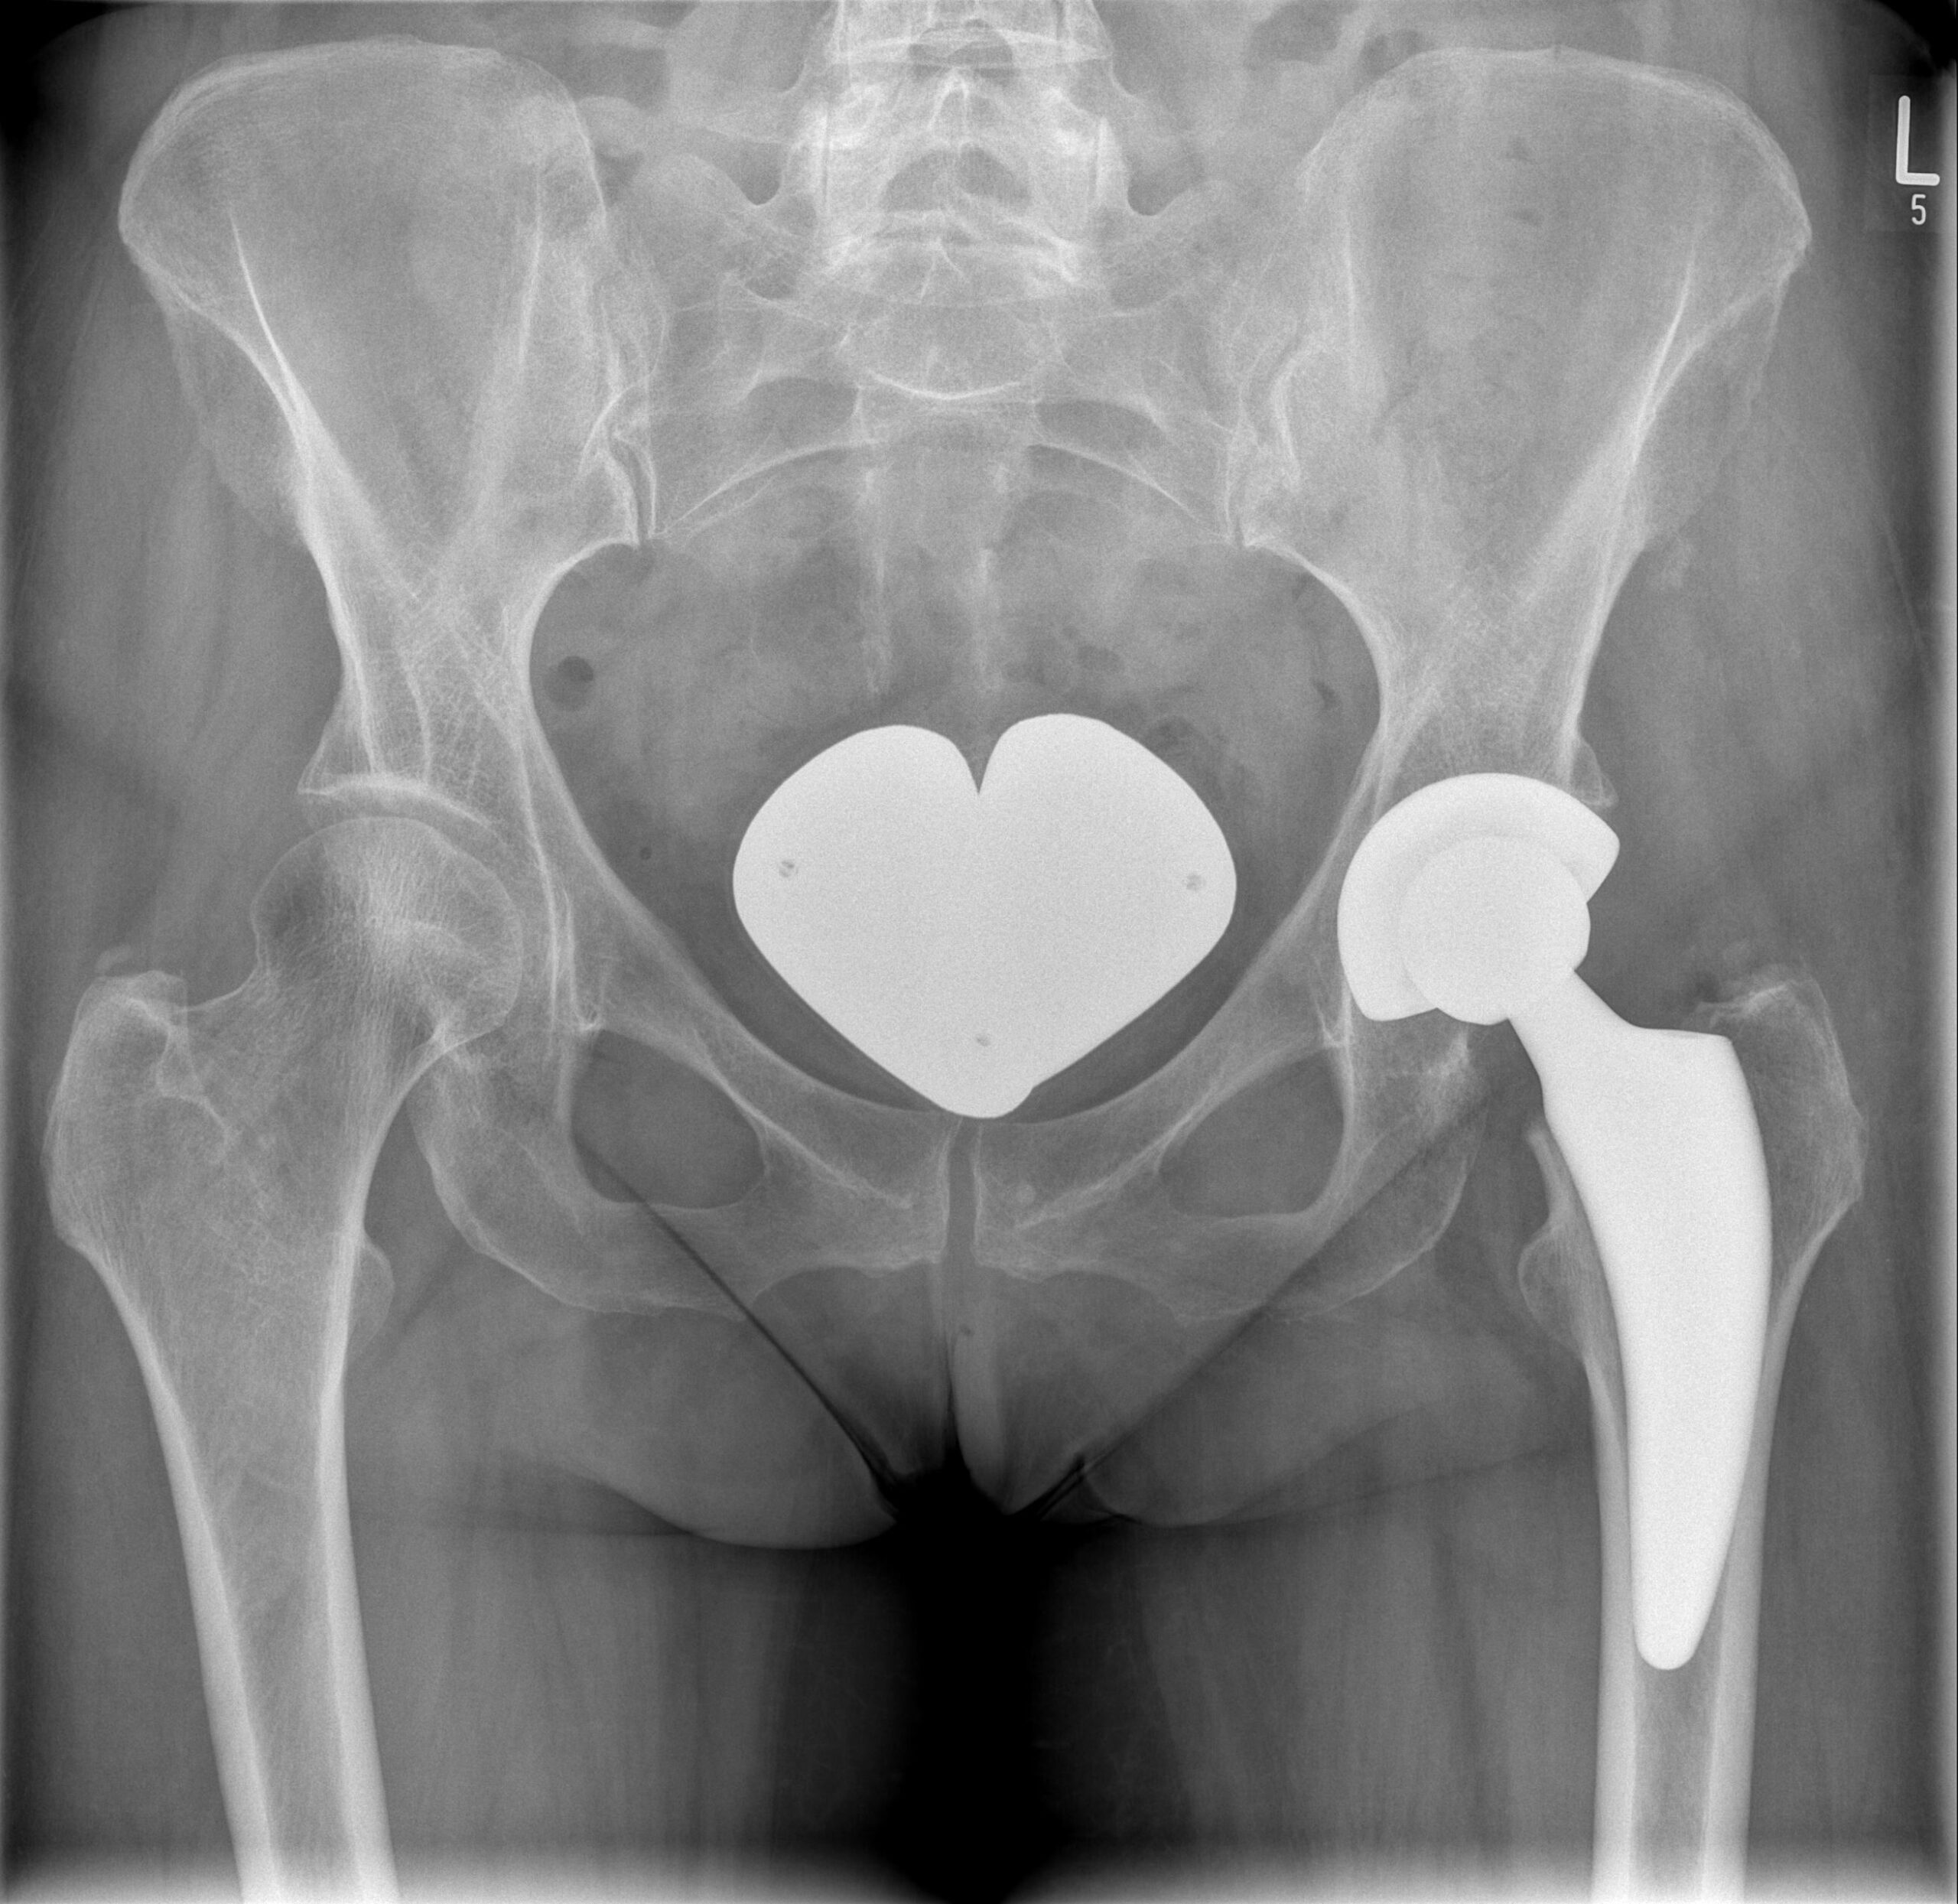

Endoprothetik von Hüft- und Kniegelenk

Auch: „künstlicher Gelenkersatz“.

Eine Endoprothese ist der künstliche Ersatz eines Gelenkes. Nahezu alle Gelenke können heute endoprothetisch ersetzt werden.

Am erfolgversprechendsten ist diese Operation jedoch an Hüft- und Kniegelenk, wo sie durch das Team unseres Praxiszentrums vorgenommen wird. Häufigste Ursache für den Verschleiß eines Gelenkes ist die Arthrose.